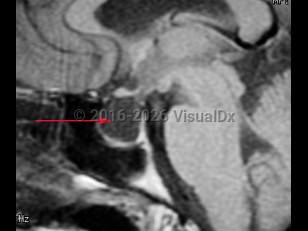

Imaging Studies image of Empty sella syndrome - imageId=8342670. Click to open in gallery.  caption: '<span>MRI demonstrating empty sella turcica.</span>'

MRI demonstrating empty sella turcica.